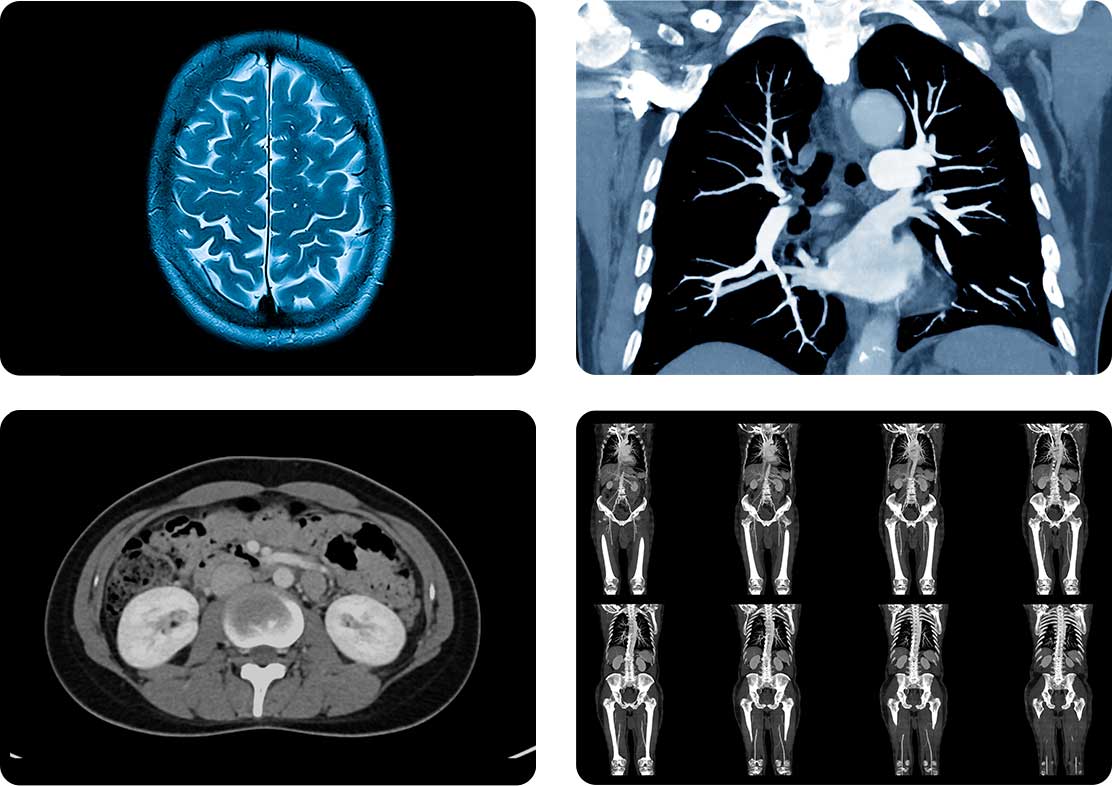

A CT scan (Computed Tomography) is a widely used diagnostic imaging procedure that combines advanced X-ray technology with sophisticated computer processing to generate detailed cross-sectional images of the body. These images provide precise visualization of organs, bones, blood vessels, and soft tissues, supporting accurate evaluation of injury, disease, and structural abnormalities.

CT imaging plays a critical role in modern diagnostic care by delivering fast, high-resolution results that inform clinical decision-making and treatment planning. Advanced imaging technology is designed to optimize image clarity while maintaining appropriate safety standards, helping ensure reliable, clinically actionable findings.